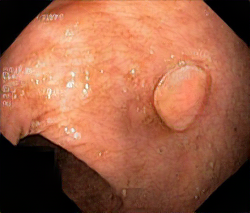

We have used a polyp dataset published with HyperKvasir dataset [51], which consists of polyp findings extracted from endoscopy examinations. HyperKvasir contains polyp images with corresponding segmentation masks annotated by medical experts. We use only this polyp dataset as a case study because of the time and resource-consuming training process of the SinGAN-Seg pipeline. However, the SinGAN-Seg model and pipeline can be used for any segmentation dataset.

A few sample images and the corresponding masks of the polyp dataset in HyperKvasir are shown in Fig 2. The polyp images are RGB images. The masks of the polyp images are single-channel images with white () for true pixels, which represent polyp regions, and black () for false pixels, which represent clean colon or background regions. In this dataset, there are different sizes of polyps. The distribution of polyp sizes as a percentage of the full image size is presented in the histogram plot in Fig 3, and we can observe that there are more relatively small polyps compared to larger polyps. Additionally, a subset of this dataset was used to prove that the performance of segmentation models trained with small datasets can be improved using our SinGAN-Seg pipeline, and the whole dataset was used to show the effect of using SinGAN-Seg generated synthetic images instead of a large dataset which has enough data to train segmentation models. In this regard, this dataset was used for two purposes: